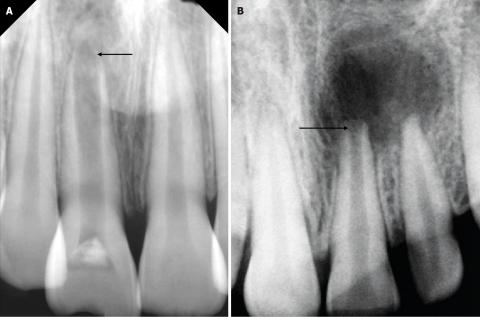

Both Image A and Image B show a dark, well-defined radiolucent area surrounding the root apex of one of the anterior teeth. This appearance is consistent with:

The normal white cortical outline around the root tip is not clearly visible. Loss of the lamina dura typically indicates a non-vital pulp and chronic inflammation.

This suggests ongoing inflammatory changes around the root.

The dark zone indicates bone loss caused by chronic infection. This usually results from long-standing pulp death or untreated decay or trauma.

The visible crowns appear intact, but the root area strongly suggests the tooth is no longer vital.